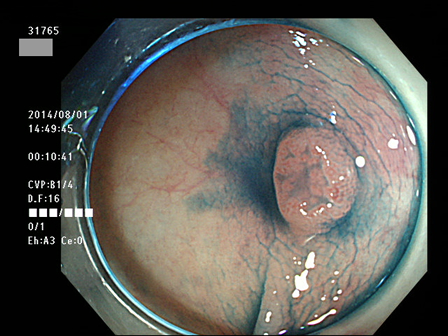

上記100名より抽出した平坦・陥凹型腺腫(=癌化の危険が高いが見落としやすい病変)の内視鏡写真

31764 31765 31766 31767 31768 31769 31771 31774 31776 31777 31778 31779